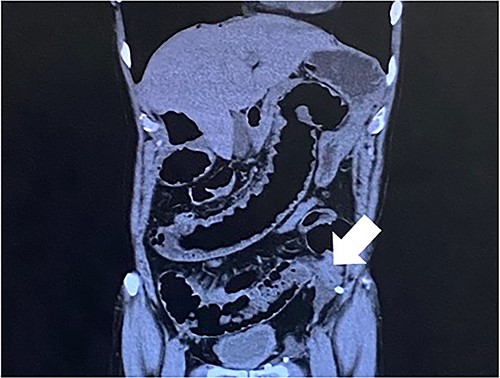

Computed tomography revealed caliber changes in the small bowel at the site of post-hernia repair in the left inguinal region (Figs 1 and 2), and the patient underwent laparoscopic surgery under general anesthesia. Intraperitoneal observation revealed that the peritoneal suture in the left inguinal region was detached, and a hole in the peritoneum had formed a hernial orifice (Fig. 4), causing SBO because of preperitoneal herniation (Fig. 3). The hernia was released, the peritoneal hole was sutured again and the surgery was completed. The postoperative course was good, and the patient was discharged from the hospital on the third postoperative day after reoperation.

The white arrow shows the small bowel incarcerating into the preperitoneal space (coronal section image).